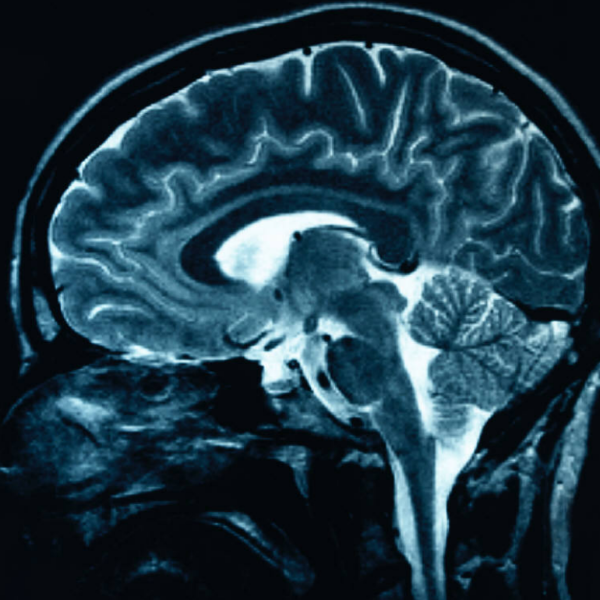

Los Angeles.- Un estudiante californiano se quejaba de violentas migrañas y los médicos finalmente hallaron al culpable: una lombriz solitaria que se había alojado en su cerebro... y casi le cuesta la vida.

Radiografías de su cerebro revelaron así la presencia del intruso, que se había instalado en un quiste.

"¡Oh! Tiene un parásito en su cabeza. Vamos a operarlo y rápido, porque si no probablemente morirá", recordó que le dijeron los médicos.

Cómo la lombriz solitaria, que en general opta por alojarse en el intestino, llegó a ese lugar, aún es un misterio tanto para los médicos como para Ortiz, que ahora manifiesta estar "feliz de estar vivo".